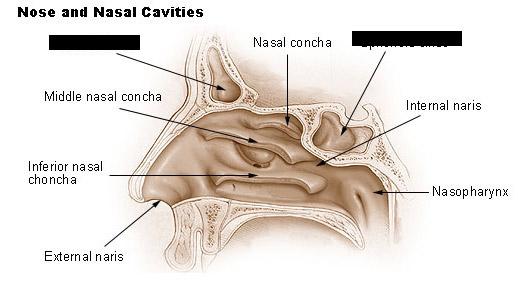

Hard/soft palate

Inferior/middle/superior concha (s.) conchae (pl.)

Nares

Nasal Cavity

Nasal septum

Naso/oro/laryngo-phraynx

Oral Cavity

Paranasal sinuses

Tongue

Uvula

Vestibule (of nasal cavity)

Vocal folds (=vocal cords)